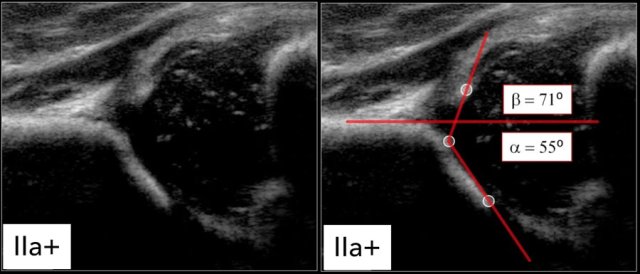

Type IIa+

The maturation process of type IIa+ hip is still within acceptable limits for age according to the table.

Type IIa

Here we see a hip with an alpha-angle of 55º.

The bony acetabular roof is less well-formed and there is a rounded acetabular bony rim.

The age of the child is 4 weeks, so we call this a type IIa.

About 90 % of newborns with Graf type IIa hips do not develop DDH.

Type IIa(+)

At the age of 6 weeks the same findings result in a type IIa(+).